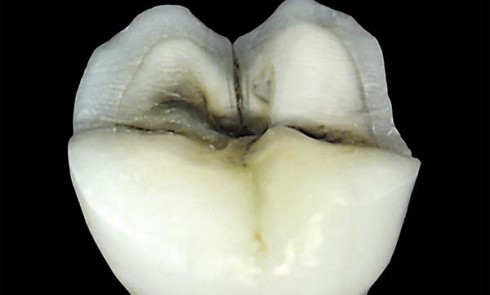

Article réservé à nos abonnés Étude du comportement des céramiques cristallines en simulateur de mastication